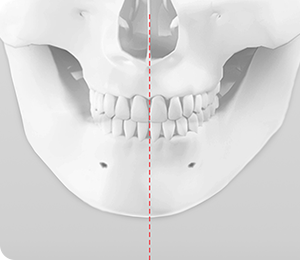

턱끝이 비대칭인 경우

턱끝의 위치나 모양이 비대칭일 경우 ㅅ절골술을 통해 비대칭을 70~90%까지 교정할 수 있습니다.